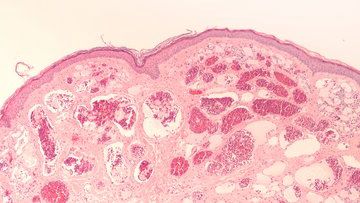

Naczyniaki powstają na skutek patologicznych zmian w obrębie naczyń krwionośnych, które powodują ich rozszerzenie. W przypadku naczyniaków wyróżnia się kilka cech charakterystycznych, które pozwalają je odróżnić od np. malformacji naczyniowych. Każdy rodzaj naczyniaka cechuje się określonym obrazem klinicznym, jednak cechą wspólną jest w tym przypadku m.in. szybkie powiększanie się zmiany w 1. roku życia dziecka, a następnie jej stopniowe zanikanie. W przypadku malformacji naczyniowych wzrost zmiany jest powolny i nie ulega ona zanikowi. Diagnostyką zmian na skórze o barwie czerwonej, która wskazuje na pochodzenie naczyniowe, powinien zająć się specjalista.

Naczyniaki powstają z różnych naczyń krwionośnych. Mogą być zlokalizowane tuż pod skórą lub znacznie głębiej, sięgając jej kolejnych warstw. Niektóre naczyniaki mogą prowadzić do wystąpienia różnych powikłań zdrowotnych, dlatego niezwykle ważne jest wczesne postawienie diagnozy oraz wdrożenie ewentualnego leczenia.

Naczyniak może powstać z wielu przyczyn, jednak nadal wszystkie nie zostały do końca poznane. Najczęściej związany jest z niegroźną mutacją genetyczną, ale niektóre naczyniaki mogą wskazywać na poważniejsze schorzenia np. zespoły wad wrodzonych. Do częstych przyczyn powstawania naczyniaków zaliczamy także zaburzenia hormonalne w przebiegu różnych schorzeń np. tarczycy, zaburzeń w funkcjonowaniu narządów wewnętrznych i innych nieprawidłowości, które pojawiają się w czasie rozwoju płodowego, podczas porodu, a także na późniejszych etapach życia. Nie wiadomo, dlaczego naczyniaki częściej występują u dziewczynek i dorosłych kobiet. Jednym z naczyniaków, które pojawiają się tylko u płci żeńskiej, są naczyniaki sromu. Lokalizują się przede wszystkim na wardze sromowej.

Naczyniaki na wargach sromowych zwykle ujawniają się w pierwszych tygodniach życia dziewczynki. Ich objawem jest początkowo różowa, niewypukła plama, która z czasem zaczyna się rozrastać. W przypadku niemowląt ujawnienie zmiany jest dość szybkie, bo na wczesnym etapie życia dzieci często odwiedzają lekarza, który dokładnie bada ich stan zdrowia. Choć naczyniak na wardze sromowej pojawia się zwykle bardzo wcześnie, to może także powstać u nastolatki lub dorosłej kobiety. W zależności od rodzaju zmiany ma ona różny wygląd.